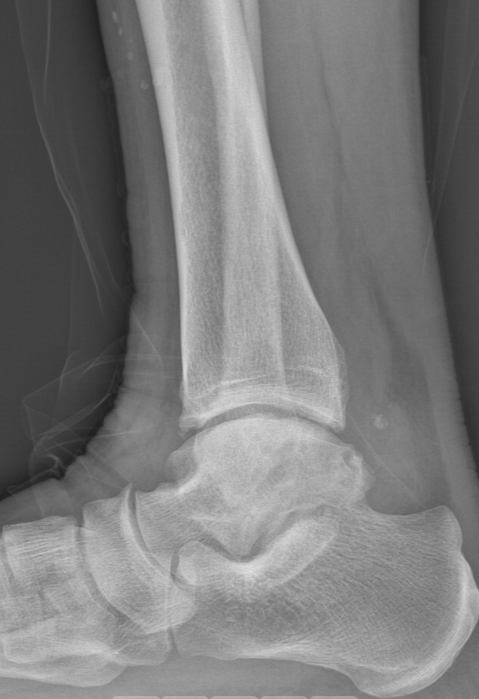

第一台手术的患者是位75岁的叔叔,被“脚脖子”痛缠了4年,疼得越来越厉害,病情已经到了严重阶段。

术前踝关节CT

术前后足力线X线

武勇主任团队给他做了3D打印导板辅助下人工全踝关节置换术。

这种手术适合踝关节病严重的患者,通过替换病变的关节结构,能帮着缓解疼痛、恢复关节活动,让老人日常走路更自在些。

术前踝关节侧位X线

术前踝关节正位X线